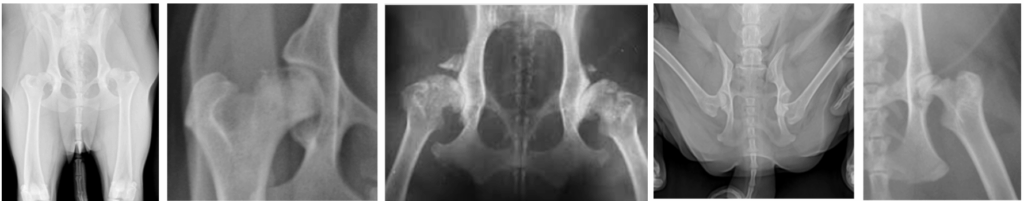

일반적인 Hip extension 촬영법 펜힙(Penn HIP) 촬영법